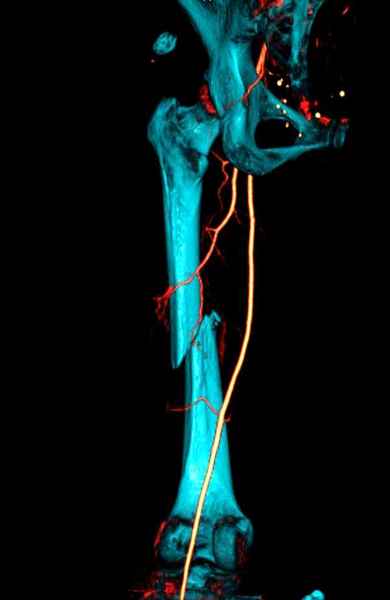

В зависимости от характера опухоли некоторые патологические переломы имеют риск кровотечения во время операции. Множественные литературные данные подтверждают, что надо проявить осторожность при интрамедуллярном остеосинтезе при неизвестных опухолях, особенно где имеется подозрение на Renal Cell Carcinoma. (RCC- hypernephroma) http://www.bonetumor.org/tumors/pages/page64.html

Со слов, больная ничем не болела, только последние 3 месяцев чувствовала боли в бедренной области. КТ брюшной полости подтвердил увеличенную правую почку. (5-6)

Для предупреждения кровотечения во время рассверливания, за день до операции провели эмболизацию сосудов питающий метастаз. http://radiology.rsnajnls.org/cgi/reprint/150/3/673.pdf (7-11, 12-15-16)

С минимальным рассверливанием и ретроградным методом провели остеосинтез бедра 12 мм гвоздем. (17-20)

Кровопотеря во время операции меньше 100 мл.